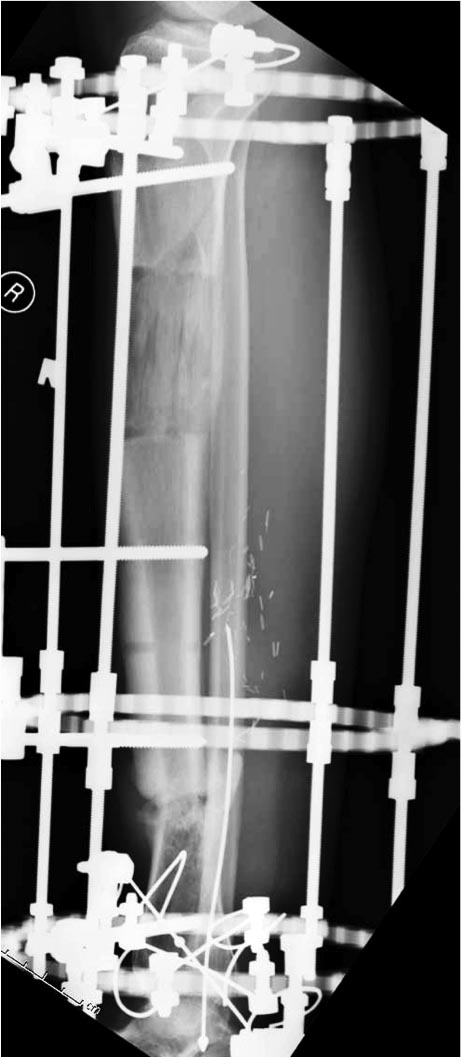

Данный случай не огнестрельная рана, а результат мотоциклетной аварии. Независимо от повреждения при таких обширных дефектах мягких и костной тканей применяется схожая тактика. Как видно, после нескольких I&D для создания “pseudo membrane” применили цилиндрический блок из цемента. Дефект мягких тканей закрыли свободным Anterior Thigh Graft. Из малого доступа цилиндр удален небольшими кусочками, а пространство заполнили бусами для освобождения пространства. По мере приближения регенерата освободили пространство удалением бус через небольшой разрез. Этап созревание регенерата можно было ускорить усилением интрамедуллярным гвоздем, но решили закончить методом Илизарова.